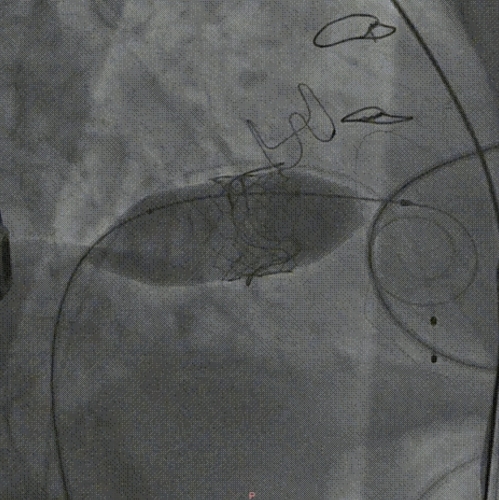

术中成功穿刺右侧股静脉,置入鞘管,精准穿刺房间隔。使用球囊预扩房间隔,随后,26号生物瓣膜经输送系统沿轨道被精准输送到位,瓣膜于最佳位置释放,爆破球囊后扩一次。术后即刻造影及经食道超声心动超声显示:人工瓣膜形态、位置良好,功能正常,仅见瓣周微量返流,左室流出道通畅,手术核心目标圆满达成,整个手术过程流畅精准。